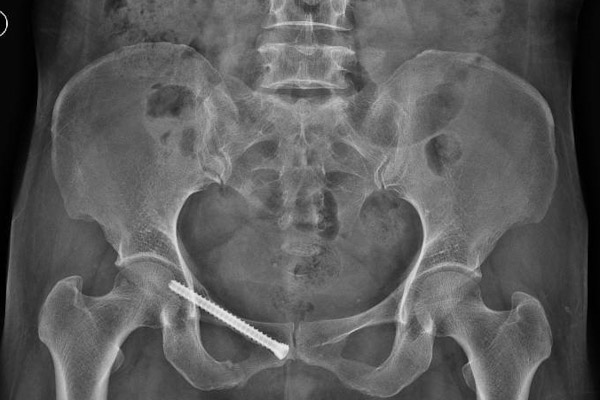

韋阿姨在干活時(shí)不慎被推車砸傷,失去了自主行走能力,被家屬送入我院創(chuàng)傷骨科,經(jīng)CT檢查,患者為骨盆骨折,需手術(shù)治療。

骨盆位置深,內(nèi)部臟器結(jié)構(gòu)豐富,血管神經(jīng)復(fù)雜,一旦發(fā)生損傷,常常導(dǎo)致相應(yīng)的血管神經(jīng)損傷和大出血,所以骨盆骨折手術(shù)一直被認(rèn)為是創(chuàng)傷骨科中最復(fù)雜的手術(shù)之一。

我院創(chuàng)傷骨科團(tuán)隊(duì)根據(jù)患者病情進(jìn)行討論,最終決定為患者行經(jīng)皮微創(chuàng)通道螺釘固定術(shù)治療。傳統(tǒng)術(shù)式需要廣泛的軟組織剝離,會(huì)引起患者術(shù)中大量失血及傷口愈合的問(wèn)題,同時(shí)傳統(tǒng)大切口可能增加傷口感染的風(fēng)險(xiǎn)。骨盆微創(chuàng)手術(shù)不但傷口小,使患者不必再忍受傳統(tǒng)手術(shù)大切口的痛苦,而且能確保骨折部位的良好復(fù)位與維持,牢固固定,為病患術(shù)后功能恢復(fù)提供了良好的前提保障。

由于骨盆骨折位置深,周邊環(huán)繞重要的神經(jīng)和血管,在這么一個(gè)完全閉合的空間環(huán)境里手術(shù),對(duì)醫(yī)生的技藝和經(jīng)驗(yàn)要求特別高。施術(shù)醫(yī)生聚精會(huì)神,按計(jì)劃選取進(jìn)針點(diǎn),在透視下將螺釘置入約8mm的狹小骨通道中,對(duì)骨折部位進(jìn)行內(nèi)固定,經(jīng)過(guò)一個(gè)小時(shí),手術(shù)完美落幕。

經(jīng)CT檢查,結(jié)果顯示骨折復(fù)位良好,骨盆環(huán)微創(chuàng)固定后穩(wěn)定性恢復(fù),在患者體表僅僅留下0.5厘米的小切口。